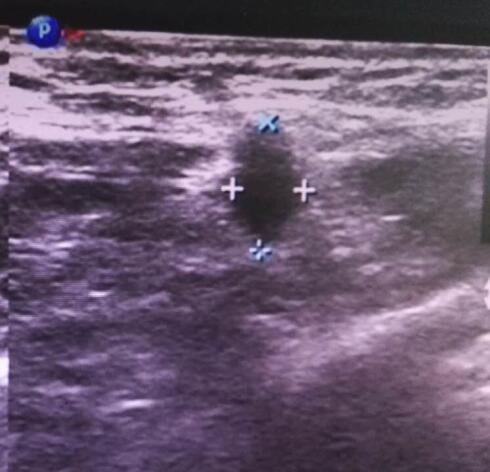

12月底,李某(男)来我院就诊,自述2年前无意中发现右侧乳房肿物,无疼痛,未行诊疗,期间肿物逐渐增大至枣样大小;首诊医师建议行超声检查。超声医师仔细扫查,发现右侧乳头后方可见大小2.7×3.2×2.2cm的实性低回声,形态尚规则,边界尚清晰,CDFI示:其内可见条状血流信号,RI:0.7。扫查患者腋窝,发现数个大小不等的l淋巴结回声,皮髓质分界不清,纵横比>1,皮质增厚,而且回声减低。这些异常特征都倾向于恶性,遂诊断为右乳包块(占位可能性大)。经手术后病理示:右乳腺乳晕下方浸润性导管癌。